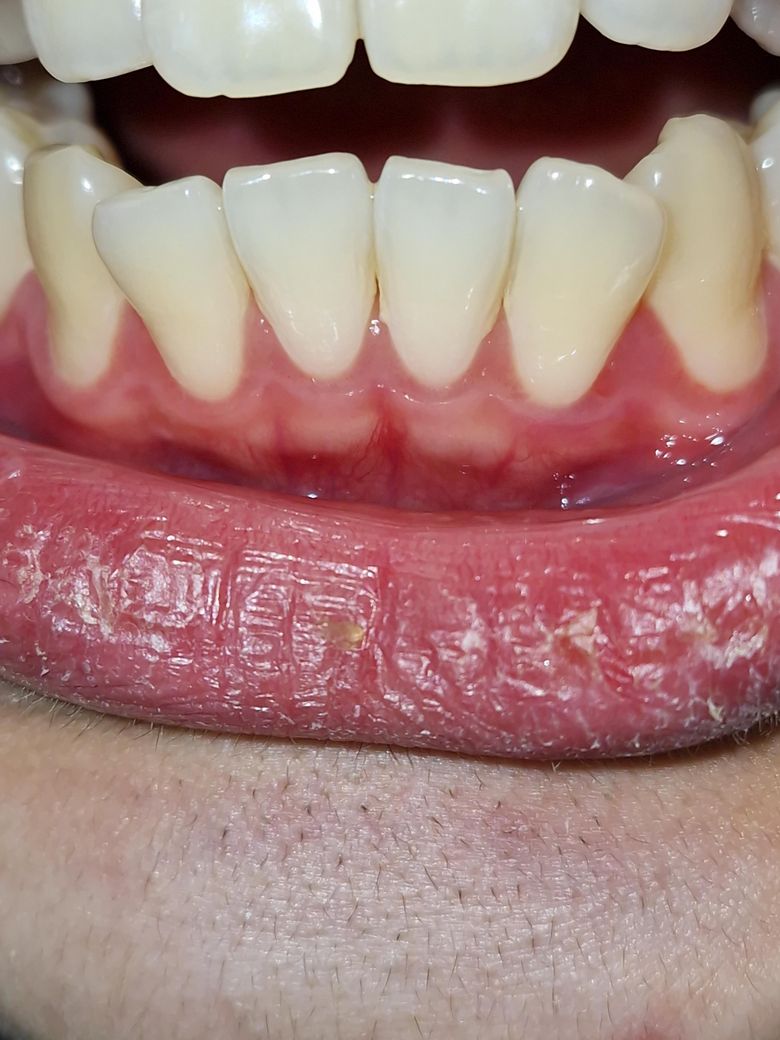

앞니 뒤쪽 잇몸이 자꾸 따끔따끔거려서 아픕니다.

이빨도 손으로 잡고 흔들면 살짝이지만 흔들리는게 눈에 보일 정도입니다. 잇몸 염증 때문일까

요?

네 잇몸에 염증이 다소 있는 상태로 보입니다. 치과가서 잇몸검진 받아보시고 스케일링, 잇몸치료 받으시고요. 평소 집에서는 바스법으로 양치해주세요.

잇몸이 따끔하고 아프면 염증이 있어서 그럴 수 있으나 치아가 흔들리는 정도라면 치과 가보셔야 합니다.

사진으로 봤을 경우에는 잇몸에 염증이 있지는 않습니다. 치아에 너무 강한 힘이 가해졌다면 일시적으로 흔들리는 느낌이 들수 있습니다.

치아에 가해지는 힘을 줄여보세요.

자세한 확인을 위해서 치과에서 진료를 받아보는 것을 권유드립니다.